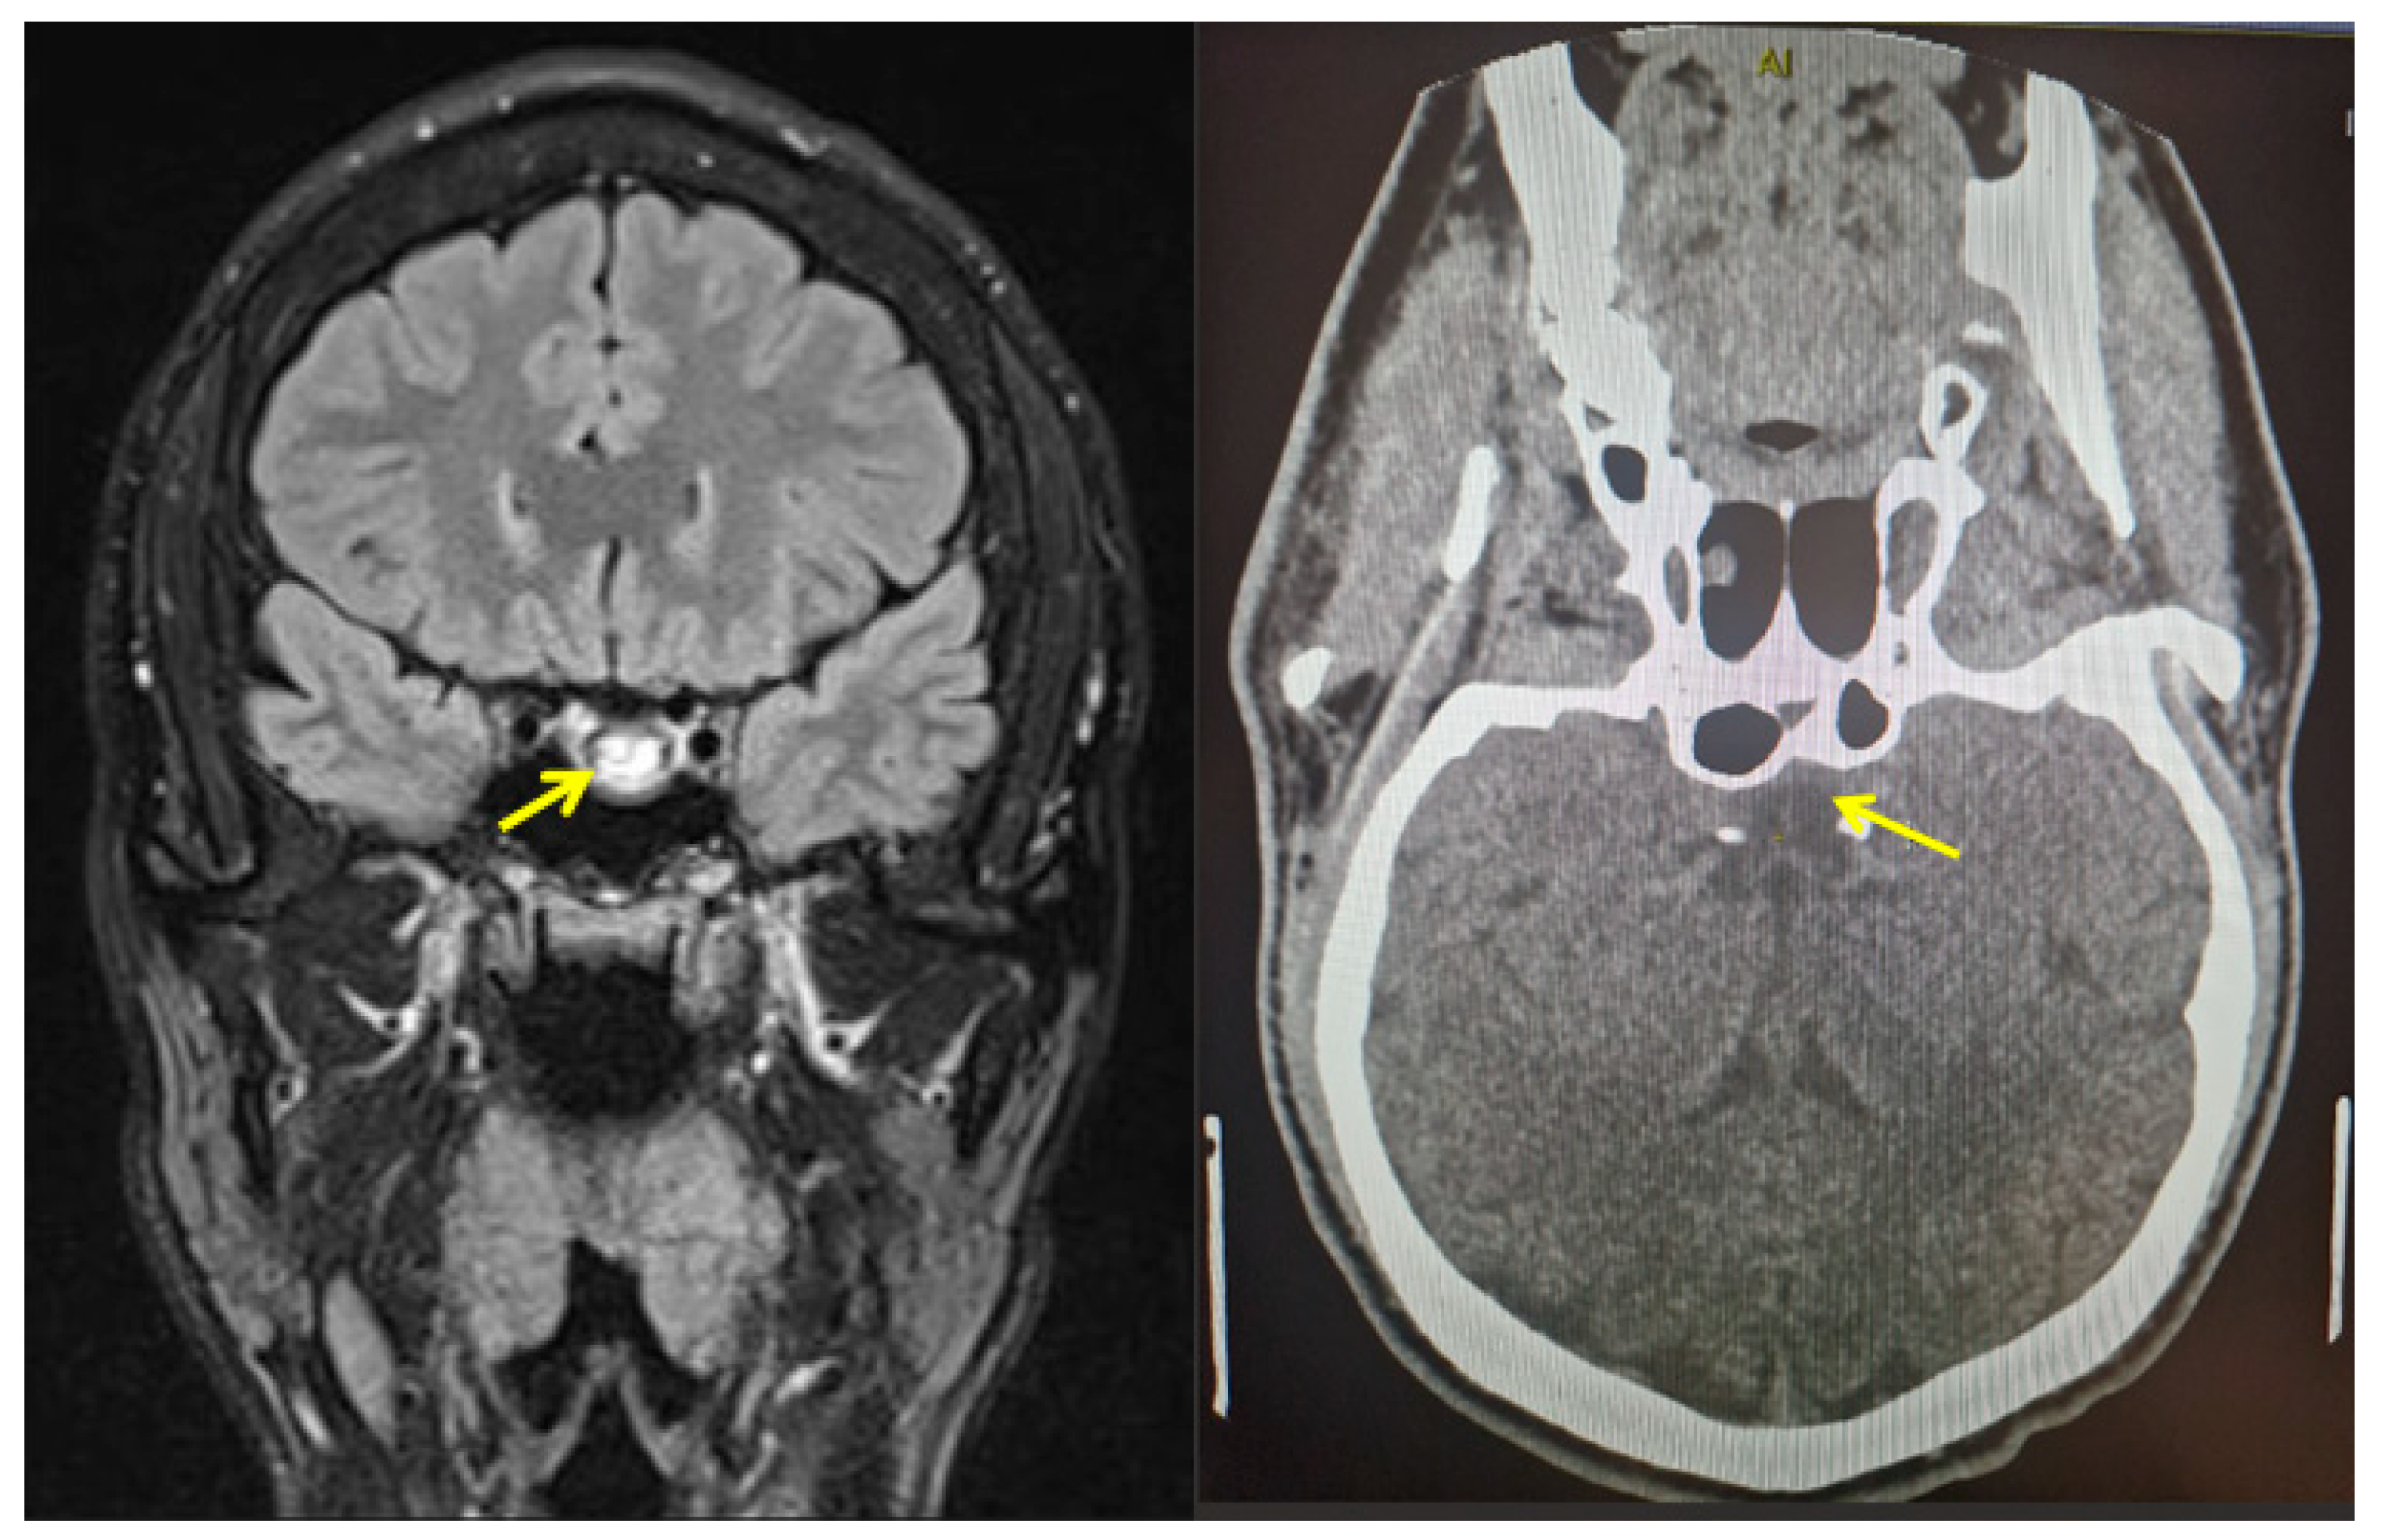

- Goyal, P.; Utz, M.; Gupta, N.; Kumar, Y.; Mangla, M.; Gupta, S.; Mangla, R. Clinical and imaging features of pituitary apoplexy and role of imaging in differentiation of clinical mimics. Quant. Imaging Med. Surg. 2018, 8, 219–231. [Google Scholar] [CrossRef]

- Boellis, A.; Di Napoli, A.; Romano, A.; Bozzao, A. Pituitary apoplexy: An update on clinical and imaging features. Insights Imaging 2014, 5, 753–762. [Google Scholar] [CrossRef]

- Vaphiades, M.S. Pituitary Ring Sign Plus Sphenoid Sinus Mucosal Thickening: Neuroimaging Signs of Pituitary Apoplexy. Neuro-Ophthalmology 2017, 41, 306–309. [Google Scholar] [CrossRef]